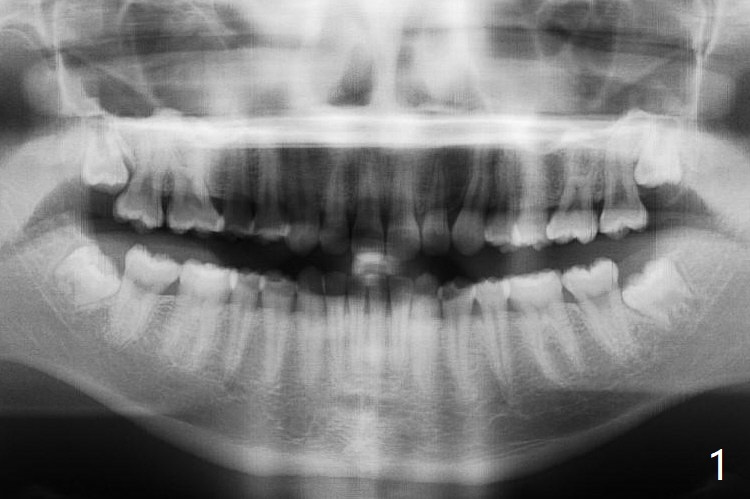

18岁女5个月前拔除右上8时疼痛明显(图一(1-2年前拍摄)),要求多打麻药拔除其余智齿。右下拔除需要切开,去骨,但是不需要分根,近中面旋转接近颊侧;左下基本萌出,拔除不需要切口,两个牙槽窝都放置胶原塞,左侧在没有减张下用4-0 Chromic Gut suture缝合,伤口基本关闭(但愿没有裂开)。右侧外斜嵴中止于远中牙槽嵴(与去骨有关?),而左侧跨越远中牙槽窝(图二:*)。术后4-5天右侧出现干槽症,局部冲洗,几天后症状消失(PRF似乎重要),而左侧伤口没有裂开。